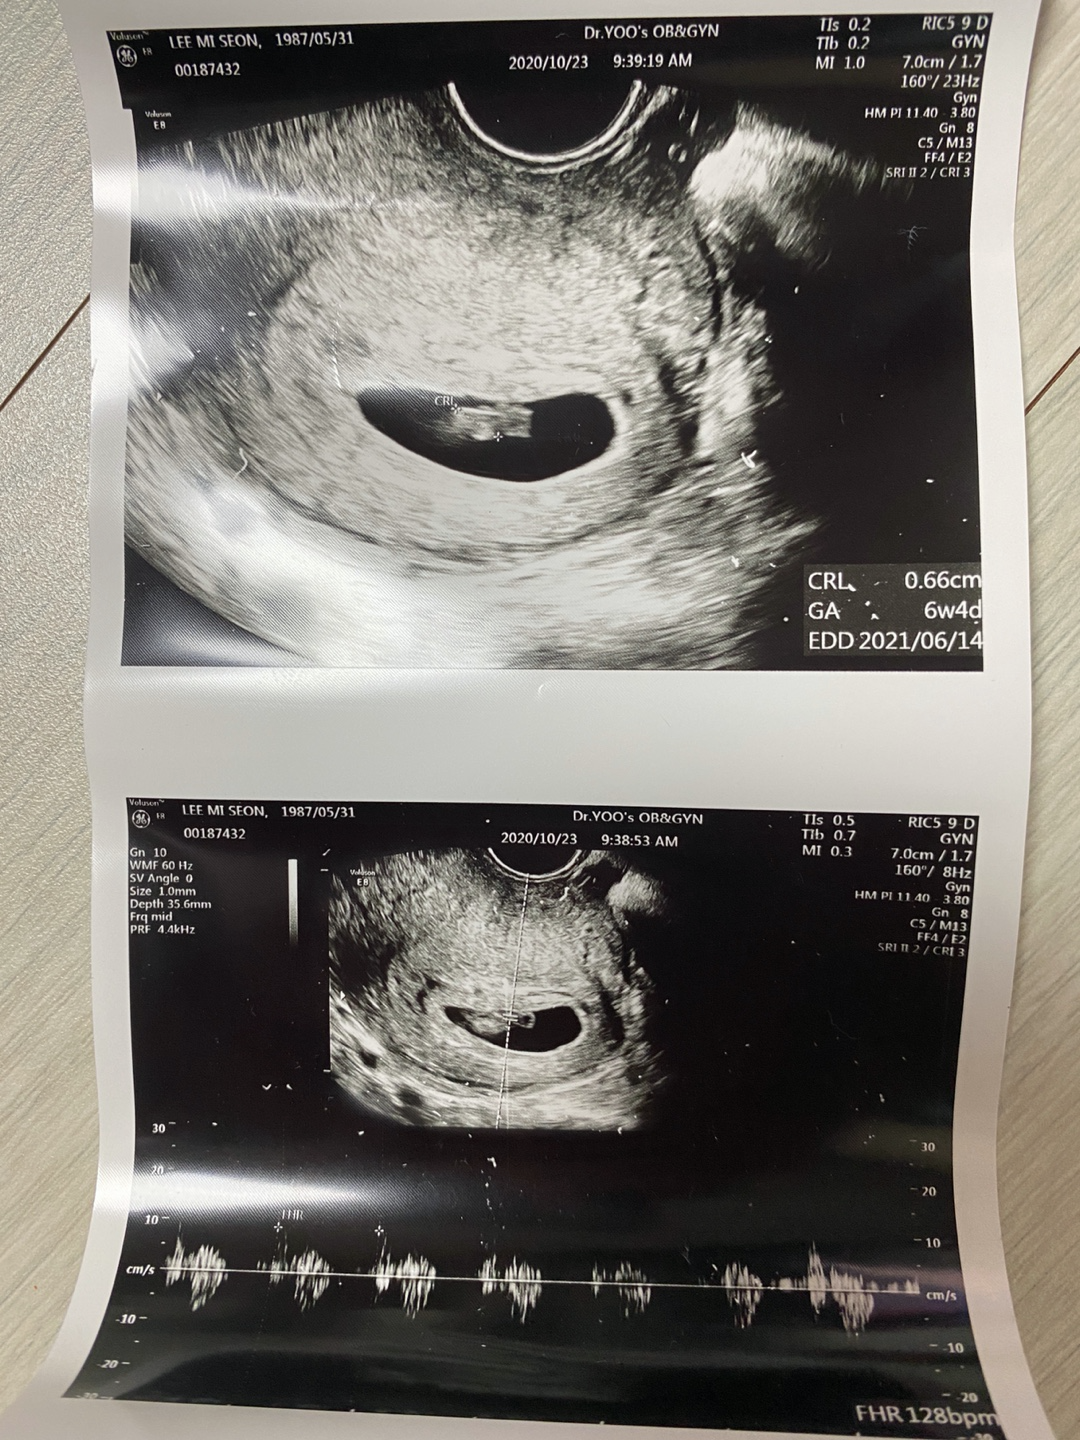

뒤이어 초음파를 보는데 아기집은 더 커져있었고 집만 있었던 공간에는 1cm도 안되는 6주차 작은 아기가 있었고 난황도 있었다.

바로 반짝반짝하는 심장을 확인하고 심장소리까지 들었다.

선생님은 6주4일 날짜를 확인해주시고 내년 6월14일 예정일과

주수에 맞춰 아기집도 아기 크기도, 심장 소리도 좋다고 했다.